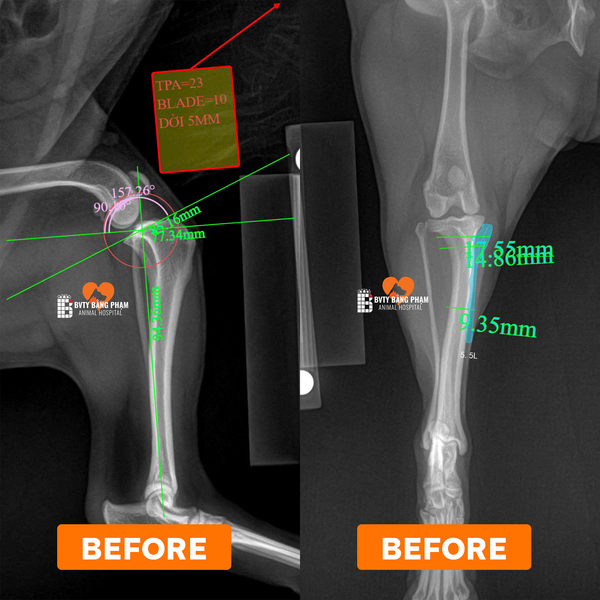

Tại Bệnh viện Thú Y Bằng Phạm, đội ngũ bác sĩ chuyên khoa chỉnh hình đã tiếp nhận và điều trị nhiều ca đứt dây chằng chéo trước (CCL) bằng kỹ thuật TPLO (Tibial Plateau Leveling Osteotomy) — một trong những phương pháp hiện đại và hiệu quả nhất hiện nay. Theo tài liệu chuyên môn, TPLO giúp thay đổi góc của mặt trượt xương chày, từ đó loại bỏ lực trượt (tibia thrust) lên khớp gối và tái lập sự ổn định mà không cần “cố gắng tái tạo hay khâu dây chằng” như cách truyền thống.

Khám – chụp X-quang, đánh giá góc xương chày, mức độ thoái hóa khớp gối

Phẫu thuật TPLO: cắt một đoạn xương chày theo hình bán nguyệt, xoay đoạn này để tạo góc mới phù hợp, sau đó cố định bằng bản kim loại và vít